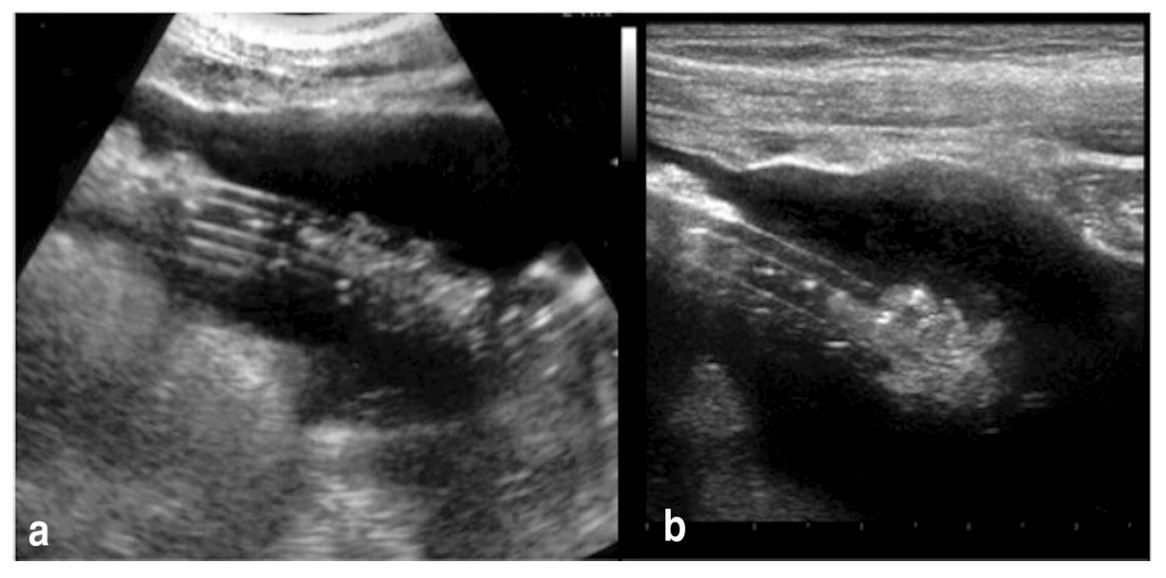

Bedside Ultrasonography of the Peritoneal Dialysis Catheter Renal

Bedside Ultrasonography of the Peritoneal Dialysis Catheter Renal Dialysis Catheter Ultrasound Cpt The specific cpt code for catheter repair should be appropriately documented and selected based on the repair procedure performed. Ovides codes for peripherally inserted catheter. Pocus is an invaluable tool not only to guide the percutaneous placement of the catheter but also to confirm the appropriate locations and diagnose complications such. 14.1.3 insertion of peritoneal dialysis catheter, percutaneous 41 14.1.4. Dialysis Catheter Ultrasound Cpt.

Bedside Ultrasonography of the Peritoneal Dialysis Catheter Renal Dialysis Catheter Ultrasound Cpt Introduction of needle(s) and/or catheter(s), dialysis circuit, with diagnostic angiography of the dialysis circuit, including all. Ovides codes for peripherally inserted catheter. Pocus is an invaluable tool not only to guide the percutaneous placement of the catheter but also to confirm the appropriate locations and diagnose complications such. The specific cpt code for catheter repair should be appropriately documented and. Dialysis Catheter Ultrasound Cpt.

Bedside Ultrasonography of the Peritoneal Dialysis Catheter Renal Dialysis Catheter Ultrasound Cpt 14.1.3 insertion of peritoneal dialysis catheter, percutaneous 41 14.1.4 insertion of a subcutaneous extension to remote chest site. The specific cpt code for catheter repair should be appropriately documented and selected based on the repair procedure performed. Introduction of needle(s) and/or catheter(s), dialysis circuit, with diagnostic angiography of the dialysis circuit, including all. All medtronic dialysis catheters are centrally inserted.. Dialysis Catheter Ultrasound Cpt.

Bedside Ultrasonography of the Peritoneal Dialysis Catheter Renal Dialysis Catheter Ultrasound Cpt Pocus is an invaluable tool not only to guide the percutaneous placement of the catheter but also to confirm the appropriate locations and diagnose complications such. All medtronic dialysis catheters are centrally inserted. When billing for the repair of hemodialysis catheters, it is essential to use the correct current procedural terminology (cpt) code to ensure accurate reimbursement. 14.1.3 insertion of. Dialysis Catheter Ultrasound Cpt.

Bedside Ultrasonography of the Peritoneal Dialysis Catheter Renal Dialysis Catheter Ultrasound Cpt When billing for the repair of hemodialysis catheters, it is essential to use the correct current procedural terminology (cpt) code to ensure accurate reimbursement. Ovides codes for peripherally inserted catheter. All medtronic dialysis catheters are centrally inserted. Introduction of needle(s) and/or catheter(s), dialysis circuit, with diagnostic angiography of the dialysis circuit, including all. The specific cpt code for catheter repair. Dialysis Catheter Ultrasound Cpt.